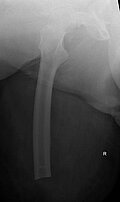

Procedere: Nach der entsprechenden Vorbereitung erfolgte im September der Ausbau der McMinn-Prothese sowie die Resektion des Schenkelhalses, ein Débridement im Bereich des Hüftgelenkes sowie die Einlage eines Spacers (i.S. einer Copal Zementeinlage) in die Hüftpfanne und im Bereich des proximalen Femurschaftes (Girdlestone Situation). Ende November 2017 erfolgte 6 Wochen nach Spacer Implantation (Abbildung 2) eine erneute Wiedervorstellung zur Punktion des Hüftgelenkes als Vorbereitung auf den Prothesenwiedereinbau. Hierbei wurde erneut ein E. coli detektiert und eine antibiogrammgerechte Antibiose mittels Ciprofloxacin 500mg 1-0-1 fortgesetzte. Die Indikation zum Spacerwechsel wurde gestellt. Der Eingriff konnte geplant Anfang Dezember durchgeführt werden.

Ende Dezember erfolgte die erste Punktion des Hüftgelenkes, bei der schließlich kein Keimnachweis erfolgte. Nach 6 weiteren Wochen konnte ebenfalls kein Keim mehr im Hüftgelenk nachgewiesen werden, so dass für März 2018 der Hüft-TEP-Wiedereinbau geplant wurde. Bei der Vorbereitung und Planung (CT Diagnostik) zeigte sich ein relativ großer knöcherner Defekt im Bereich des kranialen Acetabelums, sodass mit einem Burch-Schneider- Ring (Abbildung 3) geplant wurde.